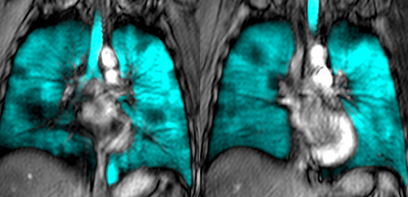

Media Release: Using lung MRI to see where and why Canadians with asthma have poor disease control

Researchers at Western University and McMaster University are developing an innovative lung imaging method that provides a unique window on asthma that is aimed at guiding and personalizing treatment for Canadians with severe, poorly controlled asthma.